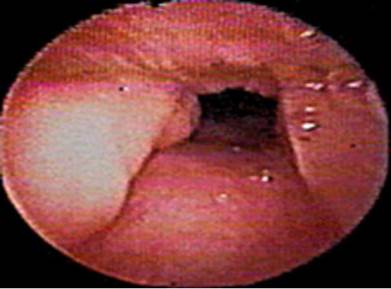

El conocimiento de la anatomía permite realizar una evaluación exacta de los posibles sitios comprometidos; para esto, se toma la VA como un diagrama de hexágono donde se ubican cada una de las estructuras (Figura 2) y, al realizar las maniobras de ronquido e inspiración forzada -maniobra de Müller tradicional-, se evalúa el tipo de colapso presentado que puede ser anteroposterior (Figura 3), lateral (Figura 4) o mixto, lo que determina la posibilidad de manejo y el posible éxito quirúrgico.

Patrón de colapso anteroposterior.

Figura 3: Patrón de colapso anteroposterior.

Fuente: Documento obtenido durante la realización del estudio.

Patrón de colapso lateral.

Figura 4: Patrón de colapso lateral.